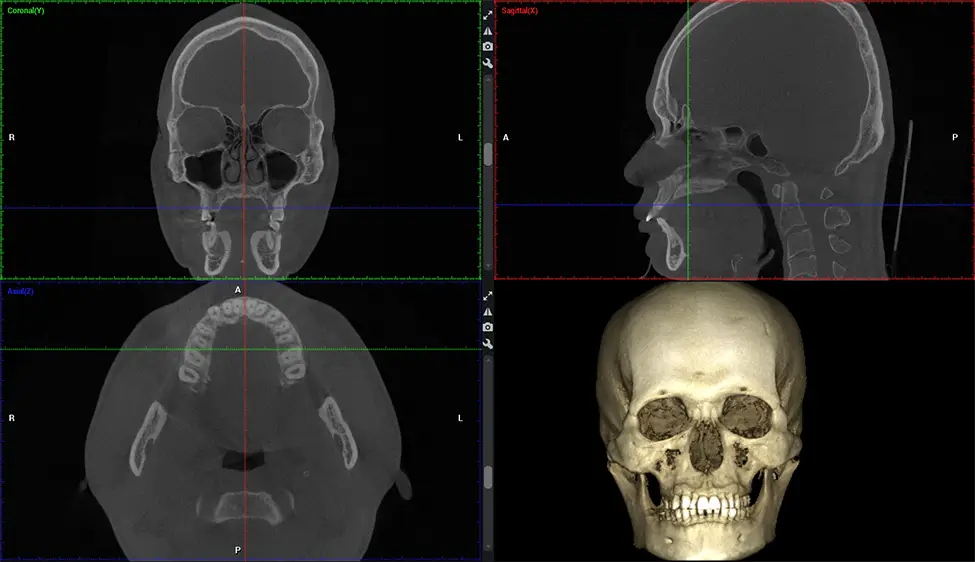

Cone Beam Computed Tomography (CBCT) is an advanced imaging technique used in dentistry and maxillofacial surgery to obtain detailed 3D images of the oral and maxillofacial structures. At Dr G Dental Studio, our CBCT scanners utilize a cone-shaped X-ray beam and a specialized detector to capture images from different angles. A computer then combines these images to create a 3D representation of the patient’s oral anatomy.

This 3D scan, called cone beam computed tomography, gives your dentist a more complete image of your oral anatomy and disease processes than a traditional X-ray. Unlike conventional X-rays, which capture a 2D image of your mouth from various angles, a 3D scan takes multiple digital X-rays for one image. It provides a complete view of your jaw, teeth, nerves, and soft tissues. This enhanced view allows dentists to detect minor issues not visible in traditional 2D scans, such as impacted wisdom teeth or bone fractures in the sinus cavity.

After the scanning process, the captured X-ray images are processed by the CBCT software, which applies algorithms to reconstruct a detailed 3D image of the scanned area. The software compiles these individual X-ray images and creates a digital 3D representation of the patient’s anatomy. The reconstructed 3D CBCT image can be viewed and analyzed by the dentist or radiologist. This image can be manipulated, rotated, and zoomed in or out to examine specific structures and evaluate the patient’s condition.